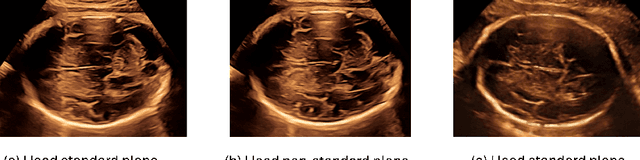

Abstract:Obstetric ultrasound image quality is crucial for accurate diagnosis and monitoring of fetal health. However, producing high-quality standard planes is difficult, influenced by the sonographer's expertise and factors like the maternal BMI or the fetus dynamics. In this work, we propose using diffusion-based counterfactual explainable AI to generate realistic high-quality standard planes from low-quality non-standard ones. Through quantitative and qualitative evaluation, we demonstrate the effectiveness of our method in producing plausible counterfactuals of increased quality. This shows future promise both for enhancing training of clinicians by providing visual feedback, as well as for improving image quality and, consequently, downstream diagnosis and monitoring.